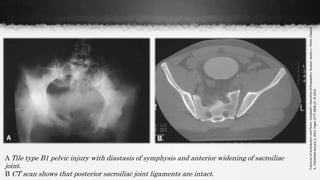

A Tile type B1 pelvic injury with diastasis of symphysis and anterior widening of sacroiliac

joint.

B CT scan shows that posterior sacroiliac joint ligaments are intact.

Y-B: Anteroposterior Compression

• I Slight widening of pubic symphisis (<2,5cm) and/or aneterior SI joint;

intact posterior SI ligaments

• II Symphysis diastasis >2.5 cm, sacrospinous, sacrotuberous and anterior

SI ligament disruption, intact posterior SI ligaments (rotational instability)